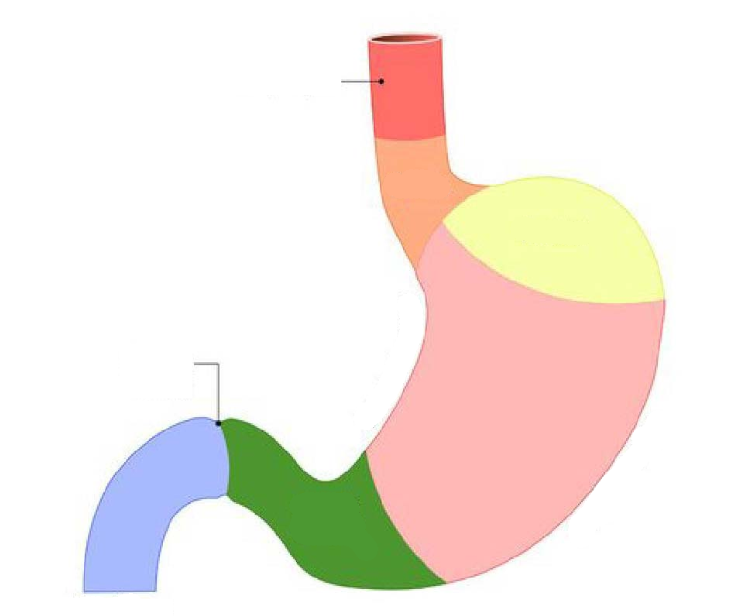

Fundus region

purple highlight

Cardia region

green highlight

Body of stomach

blue highlight

Pylorus of stomach

yellow + orange highlights

Cardiac orifice

Esophageal lumen

Pyloric sphincter

Pyloric orifice

Duodenum

blue highlight